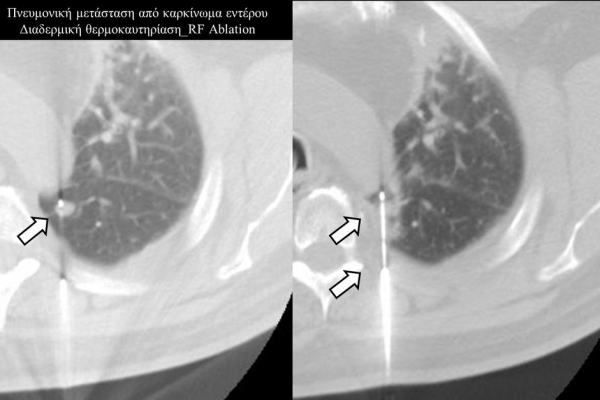

Πρόκειται για την πιο σύγχρονη τοπική θεραπεία όγκων του ήπατος, του νεφρού, του πνεύμονα, των οστών και των όγκων μαλακών μορίων. Παθοφυσιολογικά βασίζεται στην τοπική καταστροφή των καρκινικών κυττάρων με τη δημιουργία ιδιαίτερα υψηλών θερμοκρασιών εντός του όγκου. Αυτό επιτυγχάνεται με τοποθέτηση ειδικών ηλεκτροδίων εντός του όγκου υπό ακτινολογική καθοδήγηση (αξονικός τομογράφος ή υπέρηχος). Τα ηλεκτρόδια αυτά παράγουν υψηλή θερμοκρασία είτε με τη βοήθεια ραδιοσυχνοτήτων (RFablation), είτε με τη βοήθεια μικροκυμάτων (MWablation) και προκαλούν πηκτική νέκρωση των καρκινικών κυττάρων χωρίς να επηρεάζουν τα φυσιολογικά κύτταρα.Το αποτέλεσμα είναι μόνιμο.